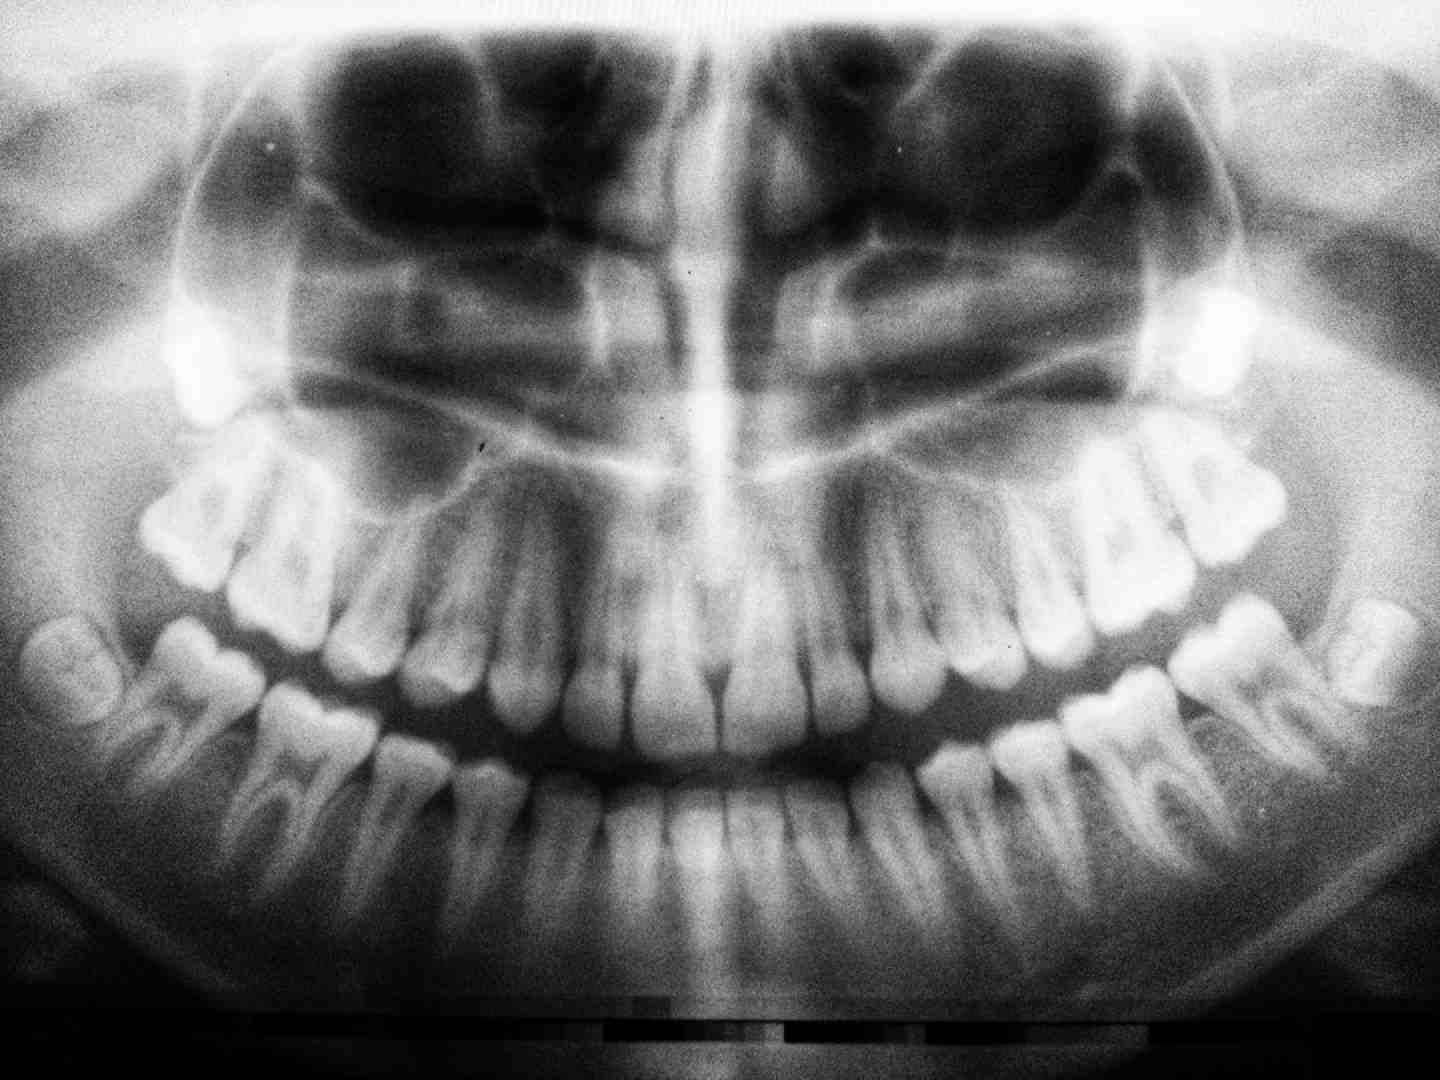

What is the procedure for dental implants?